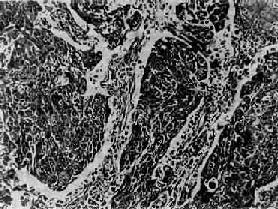

图9-32 肺低分化鳞状细胞癌 癌巢主由具有间桥的癌细胞构成,无角化珠 (2)小细胞癌:发生率在肺癌中居第二位(临床统计在40%以上,尸检统计占15%~25%)。患者男多于女(20:1),发病年龄约在35~60岁。小细胞肺癌亦多发生于肺中央部,生长迅速,转移较早,恶生度高,5年存活率仅1%~2%。小细胞癌的癌细胞很小,呈短梭形或淋巴细胞样,有些细胞呈梭形或多角型,胞浆甚少,形似裸核。癌细胞常密集成群,由结缔组织加工分隔(图9-33)。有时癌细胞围绕小血管排列成假菊形团或管状结构。小细胞肺癌起源于支气管粘膜和粘液腺内Kultschitzky细胞,是一种具有异源性内分泌功能的肿瘤。

图9-33 小细胞肺癌 短梭形癌细胞平行排列,群集成团(燕麦细胞型) (3)腺癌:发生率在肺癌中占第三位。临床统计占15%~20%,尸检统计占7%。患者女多于男(5:1),最常见于被动吸烟者。周围型肺癌中近60%为腺癌。肿块直径多在4cm以上,常累及胸膜,并常有肺门淋巴结转移。高分化腺癌癌巢呈腺管样结构(图9-34),可伴有粘液分泌;低分化腺癌的癌巢呈筛状或实体状;未分化腺癌的癌细胞呈高度异型性,可呈肉瘤样结构。